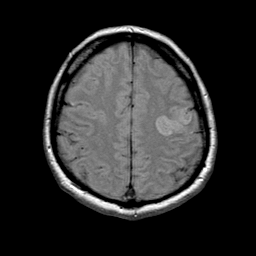

Tour 1: Next/Previous/Start: This acute cerebral infarction can be seen to involve the left pre- central gyrus. Abnormally bright signal is seen here because of the presence of excess water which has a prolonged relaxation time. As tissue has become infarcted and edematous, the sulcus is no longer identifiable. Compare the infarcted side with the normal right side. As you navigate through the datasets, change between the three types of image with the buttons at right, or click on the timeline tickmark for the desired dataset.

[Home][Help][Clinical][Tour 1] Slice 18